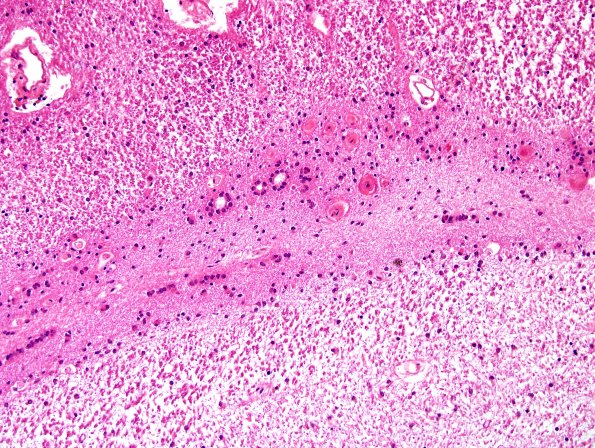

Ependymal Fusion Seam

Progressive increase in magnification illustrates the constituent elements. (H&E)